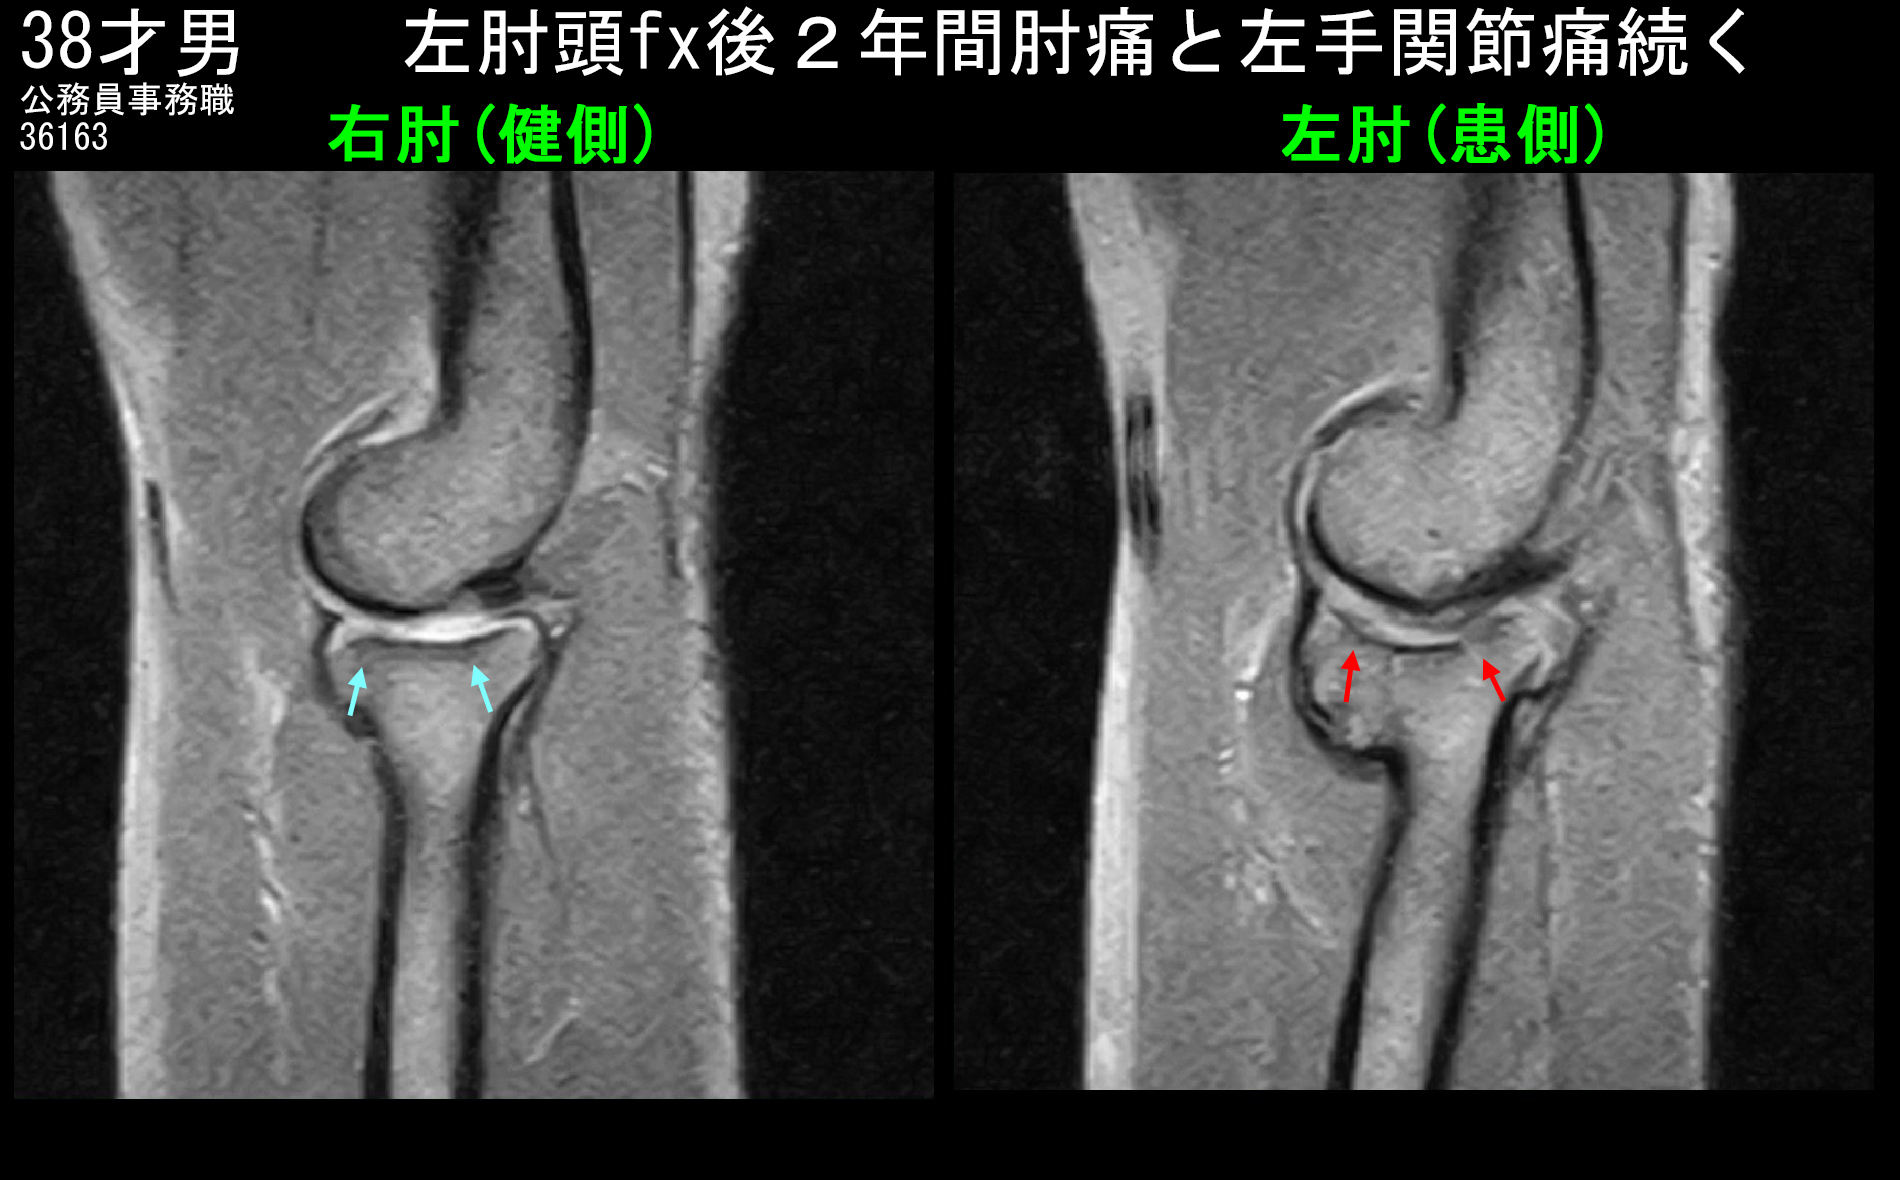

38才男MRI1.jpg

MRI検査では左肘の赤矢印(橈骨頭部)に関節面の軽微な不正像と骨のラインが断裂して骨折が少しずれて治癒していることが分かります。